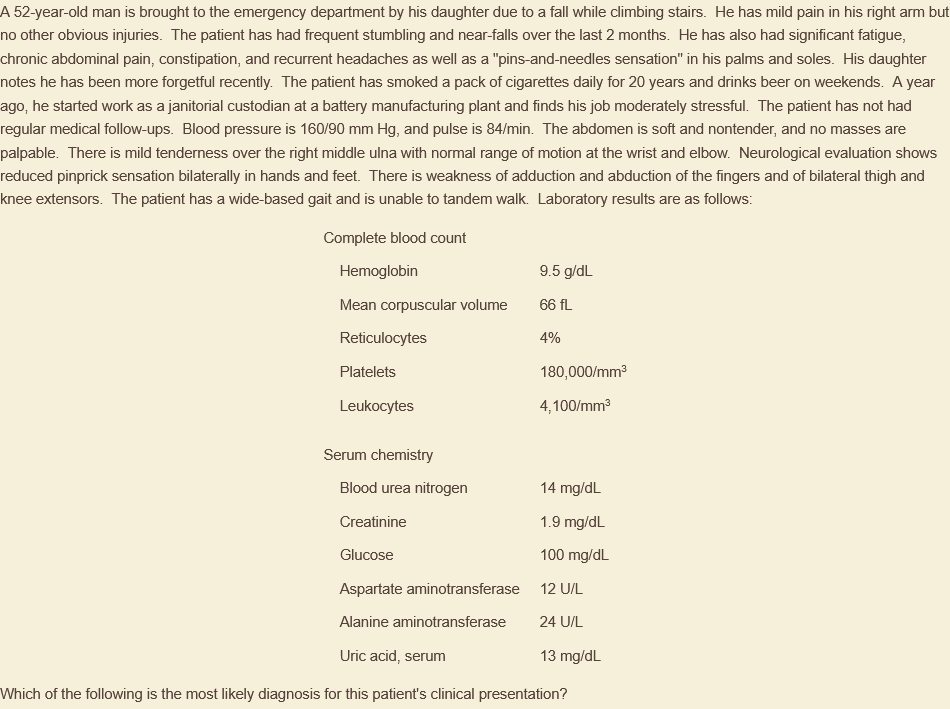

lead poisoning